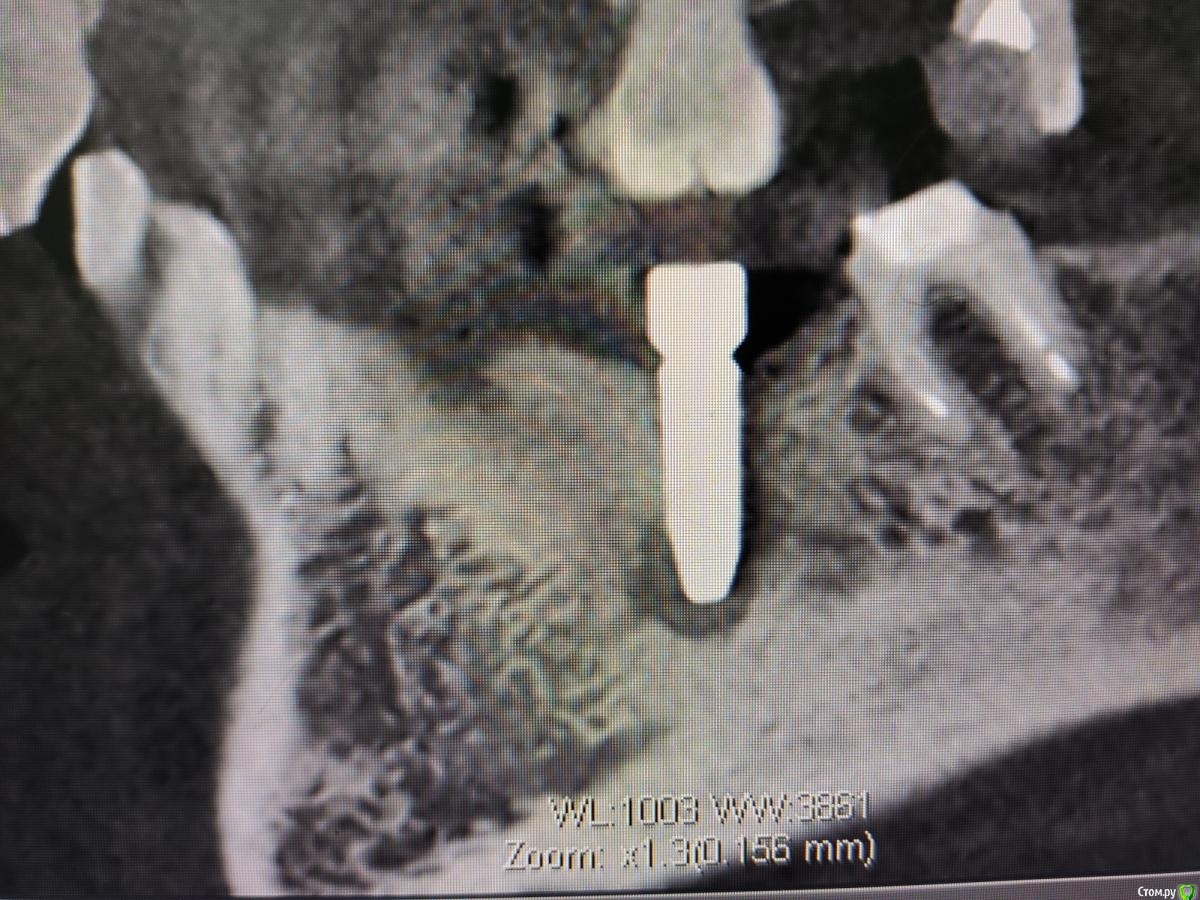

Дмитрий М Опубликовано 14 октября, 2020 Поделиться Опубликовано 14 октября, 2020 чтобы не создавать новых тем, коллеги подскажите, что за периапикальные изменения на снимке имплантация 4 мес.назад,КТ свежее, жалоб нет Ссылка на комментарий

meddikus Опубликовано 24 октября, 2020 Поделиться Опубликовано 24 октября, 2020 чтобы не создавать новых тем, коллеги подскажите, что за периапикальные изменения на снимке 1602515938806.jpg1602515938810.jpg1602515938814.jpg имплантация 4 мес.назад,КТ свежее, жалоб нет вас интересует резорбция на апексе? Ссылка на комментарий

Дмитрий М Опубликовано 25 октября, 2020 Поделиться Опубликовано 25 октября, 2020 чтобы не создавать новых тем, коллеги подскажите, что за периапикальные изменения на снимке 1602515938806.jpg1602515938810.jpg1602515938814.jpg имплантация 4 мес.назад,КТ свежее, жалоб нет вас интересует резорбция на апексе? да Ссылка на комментарий

Zolotoy255 Опубликовано 27 октября, 2020 Поделиться Опубликовано 27 октября, 2020 Переимплантит и выкручивать?очень похоже на "перирентгенит" , сделайте прицел в перпендикулярной проекции + ждите до формика. КТ аппараты в зависимости от настроек отдельно взятого могут светить по разному отсюда типо "пустоты". Просто ждите RG контроль 1 мес, 3 мес, на этапе формика поймете когда откроете. Думаю истин не открыл но дома скучно. Ссылка на комментарий

Zolotoy255 Опубликовано 27 октября, 2020 Поделиться Опубликовано 27 октября, 2020 чтобы не создавать новых тем, коллеги подскажите, что за периапикальные изменения на снимке 1602515938806.jpg1602515938810.jpg1602515938814.jpg имплантация 4 мес.назад,КТ свежее, жалоб нетТут КТ бы покрутить в живую. Тяжело сказать однозначно , на нижнем фото похож на воспалительный генез хронического течения (НО это только похож) Как на самом деле.... нужно разбираться . По 3м фоткам это как со стаканом на половину заполненным водой (кому-то полу пустой , кому-то полу полный). Но что-то мне подсказывает что может найтись спец по чтению подобных случаев и выставлению диагноза с вероятностью в 99.9 % Ссылка на комментарий

Дмитрий М Опубликовано 28 октября, 2020 Поделиться Опубликовано 28 октября, 2020 Тут КТ бы покрутить в живую. Тяжело сказать однозначно , на нижнем фото похож на воспалительный генез хронического течения (НО это только похож) Как на самом деле.... нужно разбираться . По 3м фоткам это как со стаканом на половину заполненным водой (кому-то полу пустой , кому-то полу полный). Но что-то мне подсказывает что может найтись спец по чтению подобных случаев и выставлению диагноза с вероятностью в 99.9 % буду наблюдать в динамике, контрольный снимок через 2 мес,сам больше склоняюсь, что это что-то вроде фиброзной капсулы вокруг апекса импланта Ссылка на комментарий

Nazim_NV86 Опубликовано 29 октября, 2020 Поделиться Опубликовано 29 октября, 2020 что-то вроде фиброзной капсулы вокруг апекса импланта Кость там плотная. Мелкая пыль и асептический некроз. Инкапсуляция. Очень давно встречал такую картину. Тогда помню решил для себя так... Вариант Б. Переснять на RVG. И непонятно какое сечение показывает верхний аксиальный срез. 1 Ссылка на комментарий

Дмитрий М Опубликовано 29 октября, 2020 Поделиться Опубликовано 29 октября, 2020 Кость там плотная. Мелкая пыль и асептический некроз. Инкапсуляция. Очень давно встречал такую картину. Тогда помню решил для себя так... Вариант Б. Переснять на RVG. И непонятно какое сечение показывает верхний аксиальный срез. перед протезированием проверим на ой-тест и сделаем визио Ссылка на комментарий